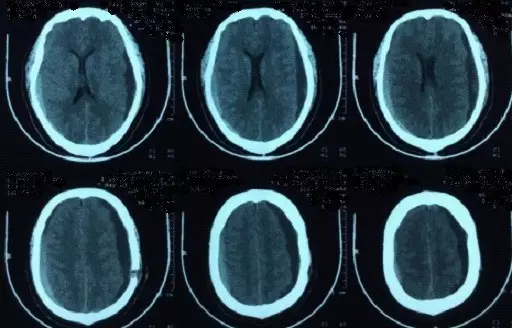

2017年5月7日上海某医院头颅CT提示:颅脑术后,双侧额颞顶部硬膜下积液积血(图4)。于2017年5月9日行双侧钻孔引流术,2017年5月12日头颅CT提示:钻孔术后改变,颅内积气(图5)。患者术后头痛症状持续加重,出现意识不清,5月15日再次复查头颅CT提示脑肿胀明显(图6),于5月17日再次行右侧硬膜下血肿清除+左侧硬膜下血肿钻孔引流术,术后患者出现脑疝,于2017年5月21日行右侧额颞顶扩大去骨瓣减压术+血肿清除术。(图7)

图5. 2017年5月12日复查头颅CT提示:钻孔术后改变,颅内积气。

图6. 2017年5月15日头颅CT显示脑沟脑池不清晰,脑肿胀明显。